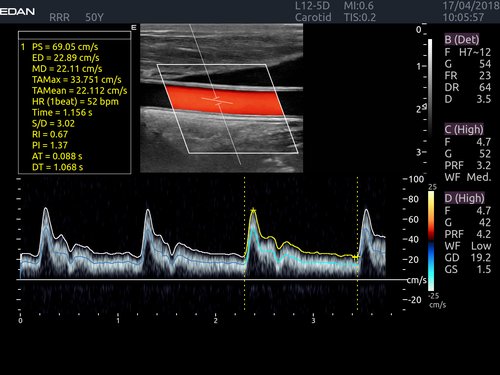

• Doppler: TAI passt sich dem Durchflusszustand an Verbesserte Kontinuität, Grenzerkennung und Ausfüllen

• Features: 3D, 4D, Farb/Doppler, Nadelführung, SW/B-Bild